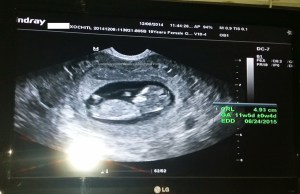

Nicki’s story of her missed miscarriage at 6 weeks 2 days, discovered at 10 weeks, 5 days, miscarried at 11 weeks, 2 days. Born at home on the eve of Forgiveness Sunday.

At the beginning of January 2015, we learned I was pregnant. My husband and I had been trying for 12 months since the loss of our first, due to an ectopic pregnancy I experienced just weeks after we got married. I had surgery to remove one of my tubes, and lost our first precious baby on October 1, 2013. I named him shortly after discovering your website “Protection”, as he was delivered on the Feast of the Holy Protection of the Theotokos. I was approximately 6wks 4 days at the time. When I got pregnant with our second (I named her “Forgiveness”), I was elated! I remember taking the pregnancy test that morning in our bathroom home alone (for probably the 30th time in the last 12 months), thinking it would be another negative result. When a saw the second line come up and realized what wonderful miracle had happened, I remember I just looked up at the ceiling and said “Thank you Lord” through tears of joy. As a precaution, I had an ultrasound to confirm that our baby was in my uterus (that was done at 5 wks 2 days), as I was at a higher risk of experiencing another ectopic. I had a gut feeling that this was a little girl. I was so sure, but did not know why. With the first pregnancy I did not have any such gut feeling, so I decided that my first must have been a boy. Only God really knows I guess.

The weeks that followed were wonderful, I had a perma smile as they say. During my sixth week, we had our parish priest come bless our home for the new year, and shared the news with him. He blessed my tummy and instructed me to drink the holy water every morning until the birth. The weeks carried on. I was not showing any major signs of pregnancy (eg. morning sickness) except that I was getting more bloated and couldn’t fit into my work attire that well anymore….and lots of peeing in the middle of the night… On Tues. February 17th (10 wks 5days), I learned through ultrasound that there was no heartbeat. They compared my first scan from the 5wk appointment to the new one, and determined our baby stopped growing at about 6 weeks. My doctor prescribed me 4 Misoprostol pills to take vaginally and sent me home that day.  She described to me that the bleeding would be like a very heavy period with more and larger clotting than usual. Not even close. To this day, I wonder if our baby was still alive when our priest blessed her with the sign of the cross over my tummy, or whether we should have had the priest come the week before so I would have started the holy water sooner. I know it’s wrong to think this way, I just can’t help it.